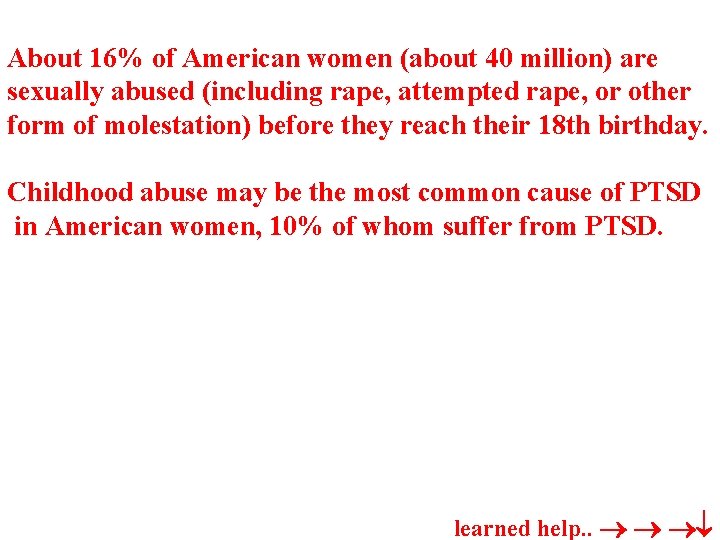

About 16% of American women (about 40 million) are sexually abused (including rape, attempted rape, or other form of molestation) before they reach their 18 th birthday. Childhood abuse may be the most common cause of PTSD in American women, 10% of whom suffer from PTSD. learned help. .